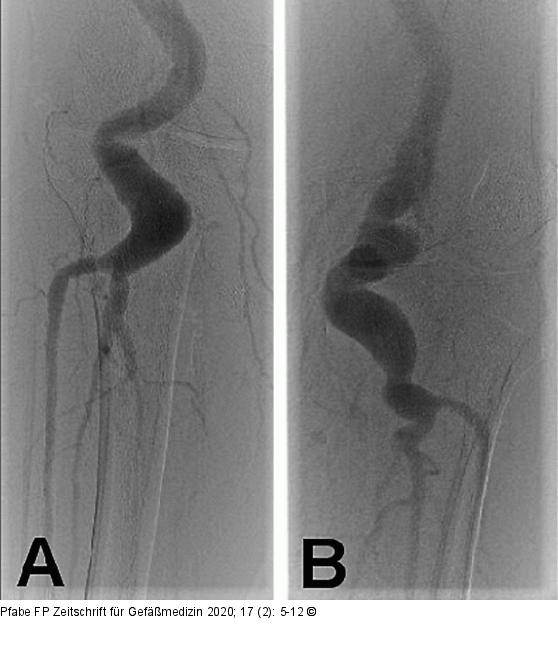

Abbildung 1A-B: Bilaterales PAA Angiographische Darstellung eines bilateralen PAA bei Arteriomegalie unter Einbeziehung des P-III-Segments bei stark elongiertem Gefäßverlauf. (A): PAA rechts; (B): PAA links. |

Abbildung 1A-B: Bilaterales PAA

Angiographische Darstellung eines bilateralen PAA bei Arteriomegalie unter Einbeziehung des P-III-Segments bei stark elongiertem Gefäßverlauf. (A): PAA rechts; (B): PAA links. |